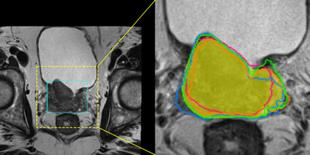

Accurate magnetic resonance imaging (MRI) segmentation is crucial for clinical decision-making, but remains labor-intensive when performed manually. Convolutional neural network (CNN)-based methods can be accurate and efficient, but often generalize poorly to MRI's variable contrast, intensity inhomogeneity, and protocols. Although the transformer-based Segment Anything Model (SAM) has demonstrated remarkable generalizability in natural images, existing adaptations often treat MRI as another imaging modality, overlooking these modality-specific challenges. We present SAMRI, an MRI-specialized SAM trained and validated on 1.1 million labeled MR slices spanning whole-body organs and pathologies. We demonstrate that SAM can be effectively adapted to MRI by simply fine-tuning its mask decoder using a two-stage strategy, reducing training time by 94% and trainable parameters by 96% versus full-model retraining. Across diverse MRI segmentation tasks, SAMRI achieves a mean Dice of 0.87, delivering state-of-the-art accuracy across anatomical regions and robust generalization on unseen structures, particularly small and clinically important structures.